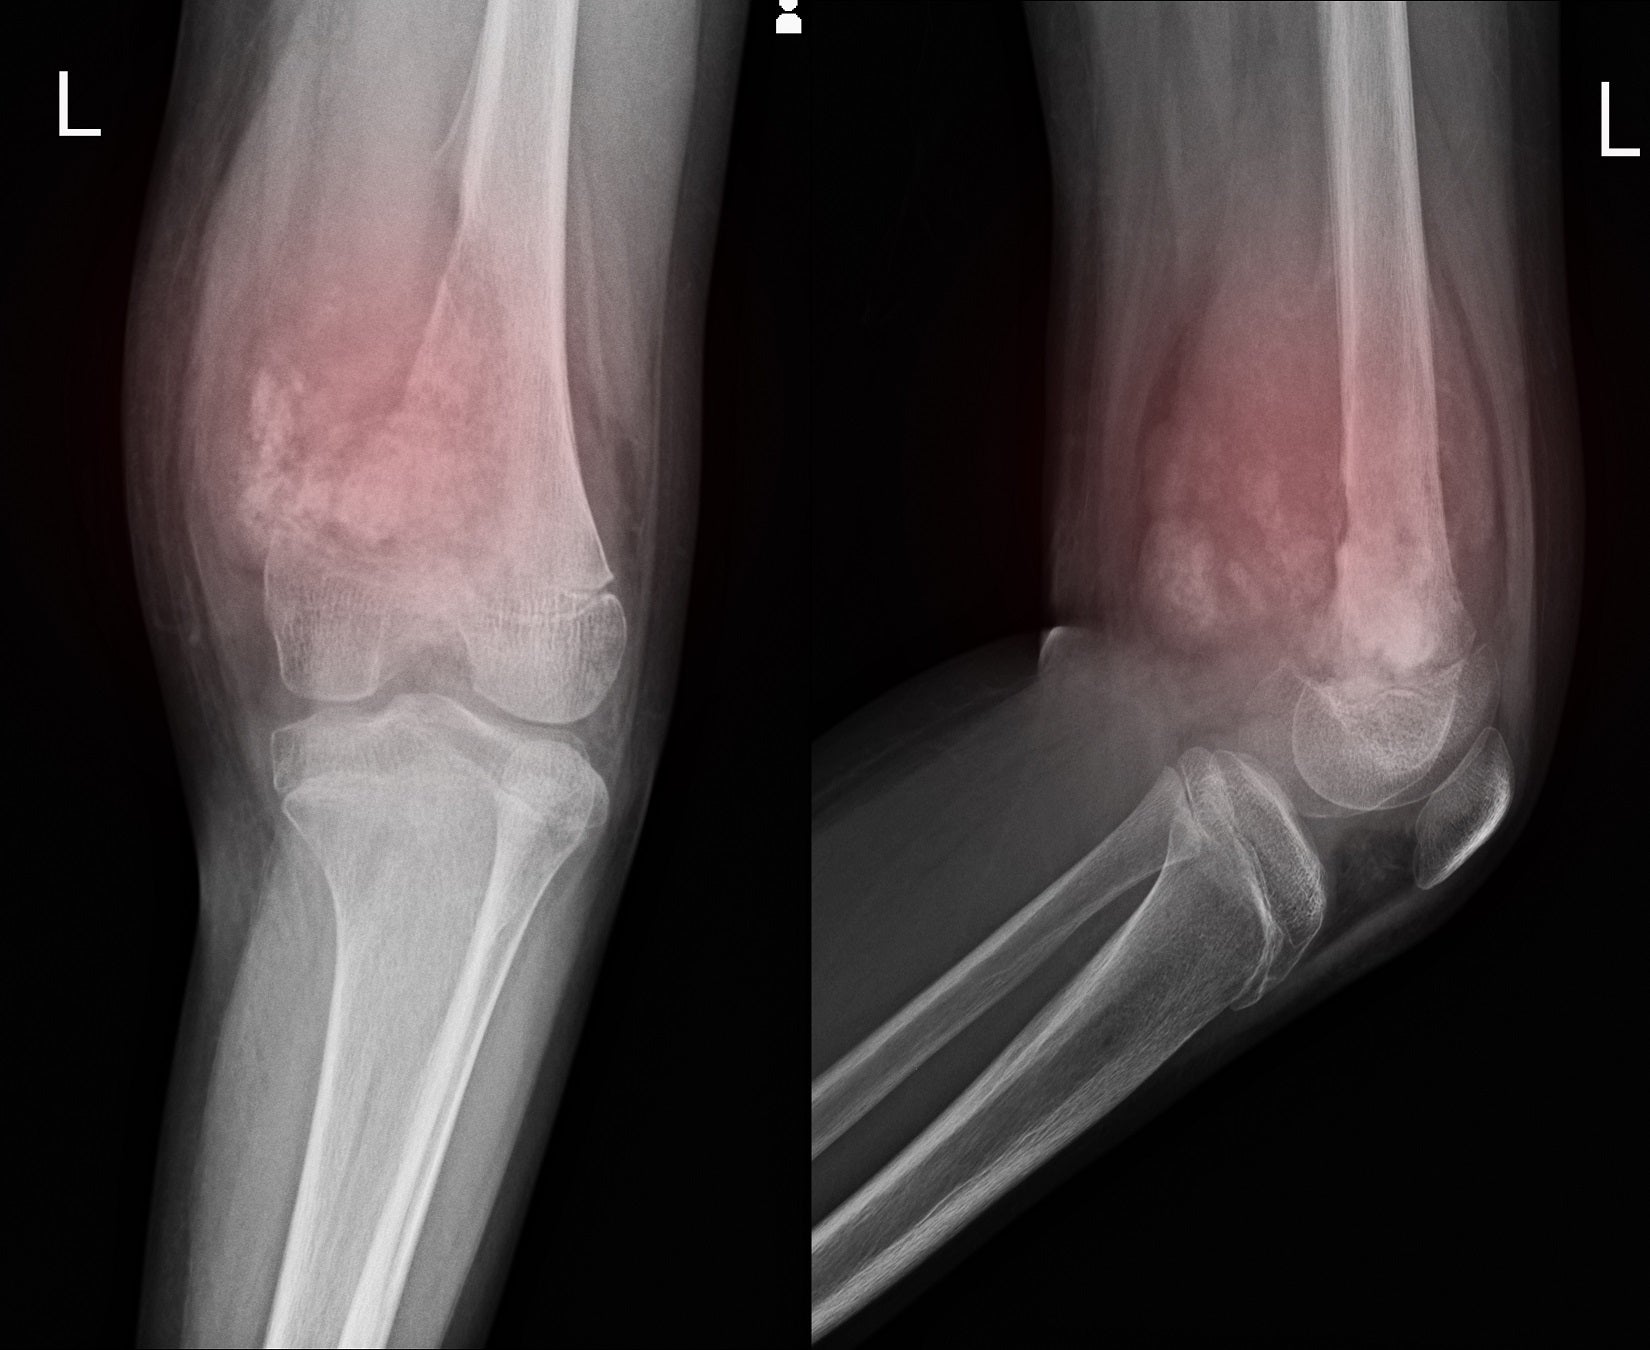

Prepatellar bursitis wikidoc